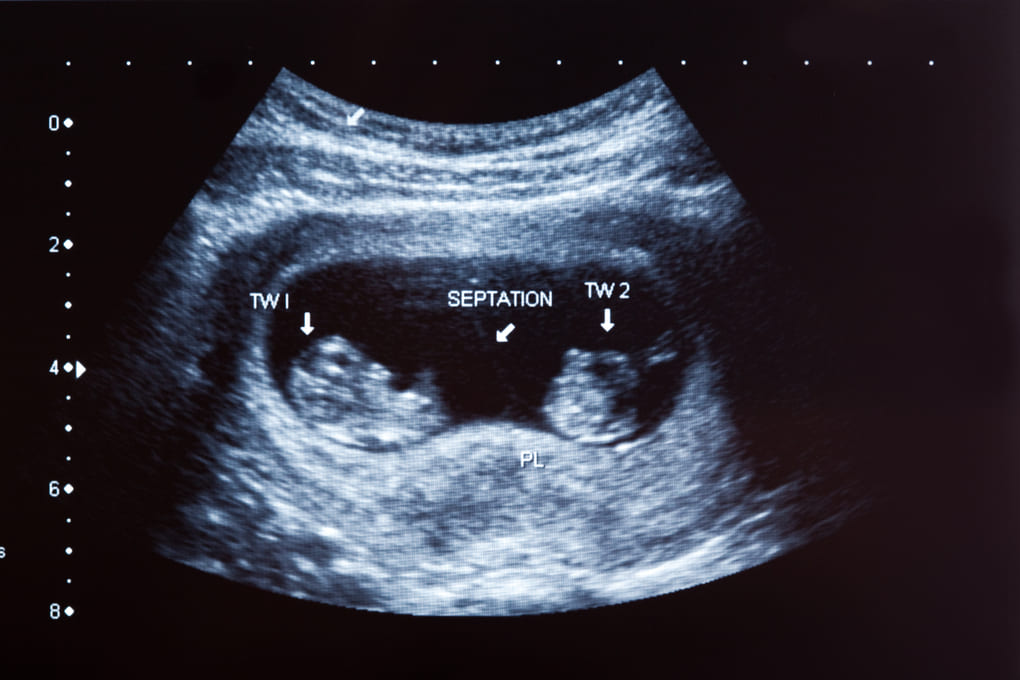

Los embarazos múltiples se dividen principalmente en dos grupos: gemelos idénticos y mellizos. Los gemelos idénticos surgen cuando un único óvulo es fertilizado por un espermatozoide y posteriormente se divide en dos embriones, compartiendo el mismo ADN. En contraste, los mellizos son el resultado de dos óvulos diferentes fecundados por espermatozoides distintos, lo cual les otorga la posibilidad de tener diferentes sexos y características físicas únicas.